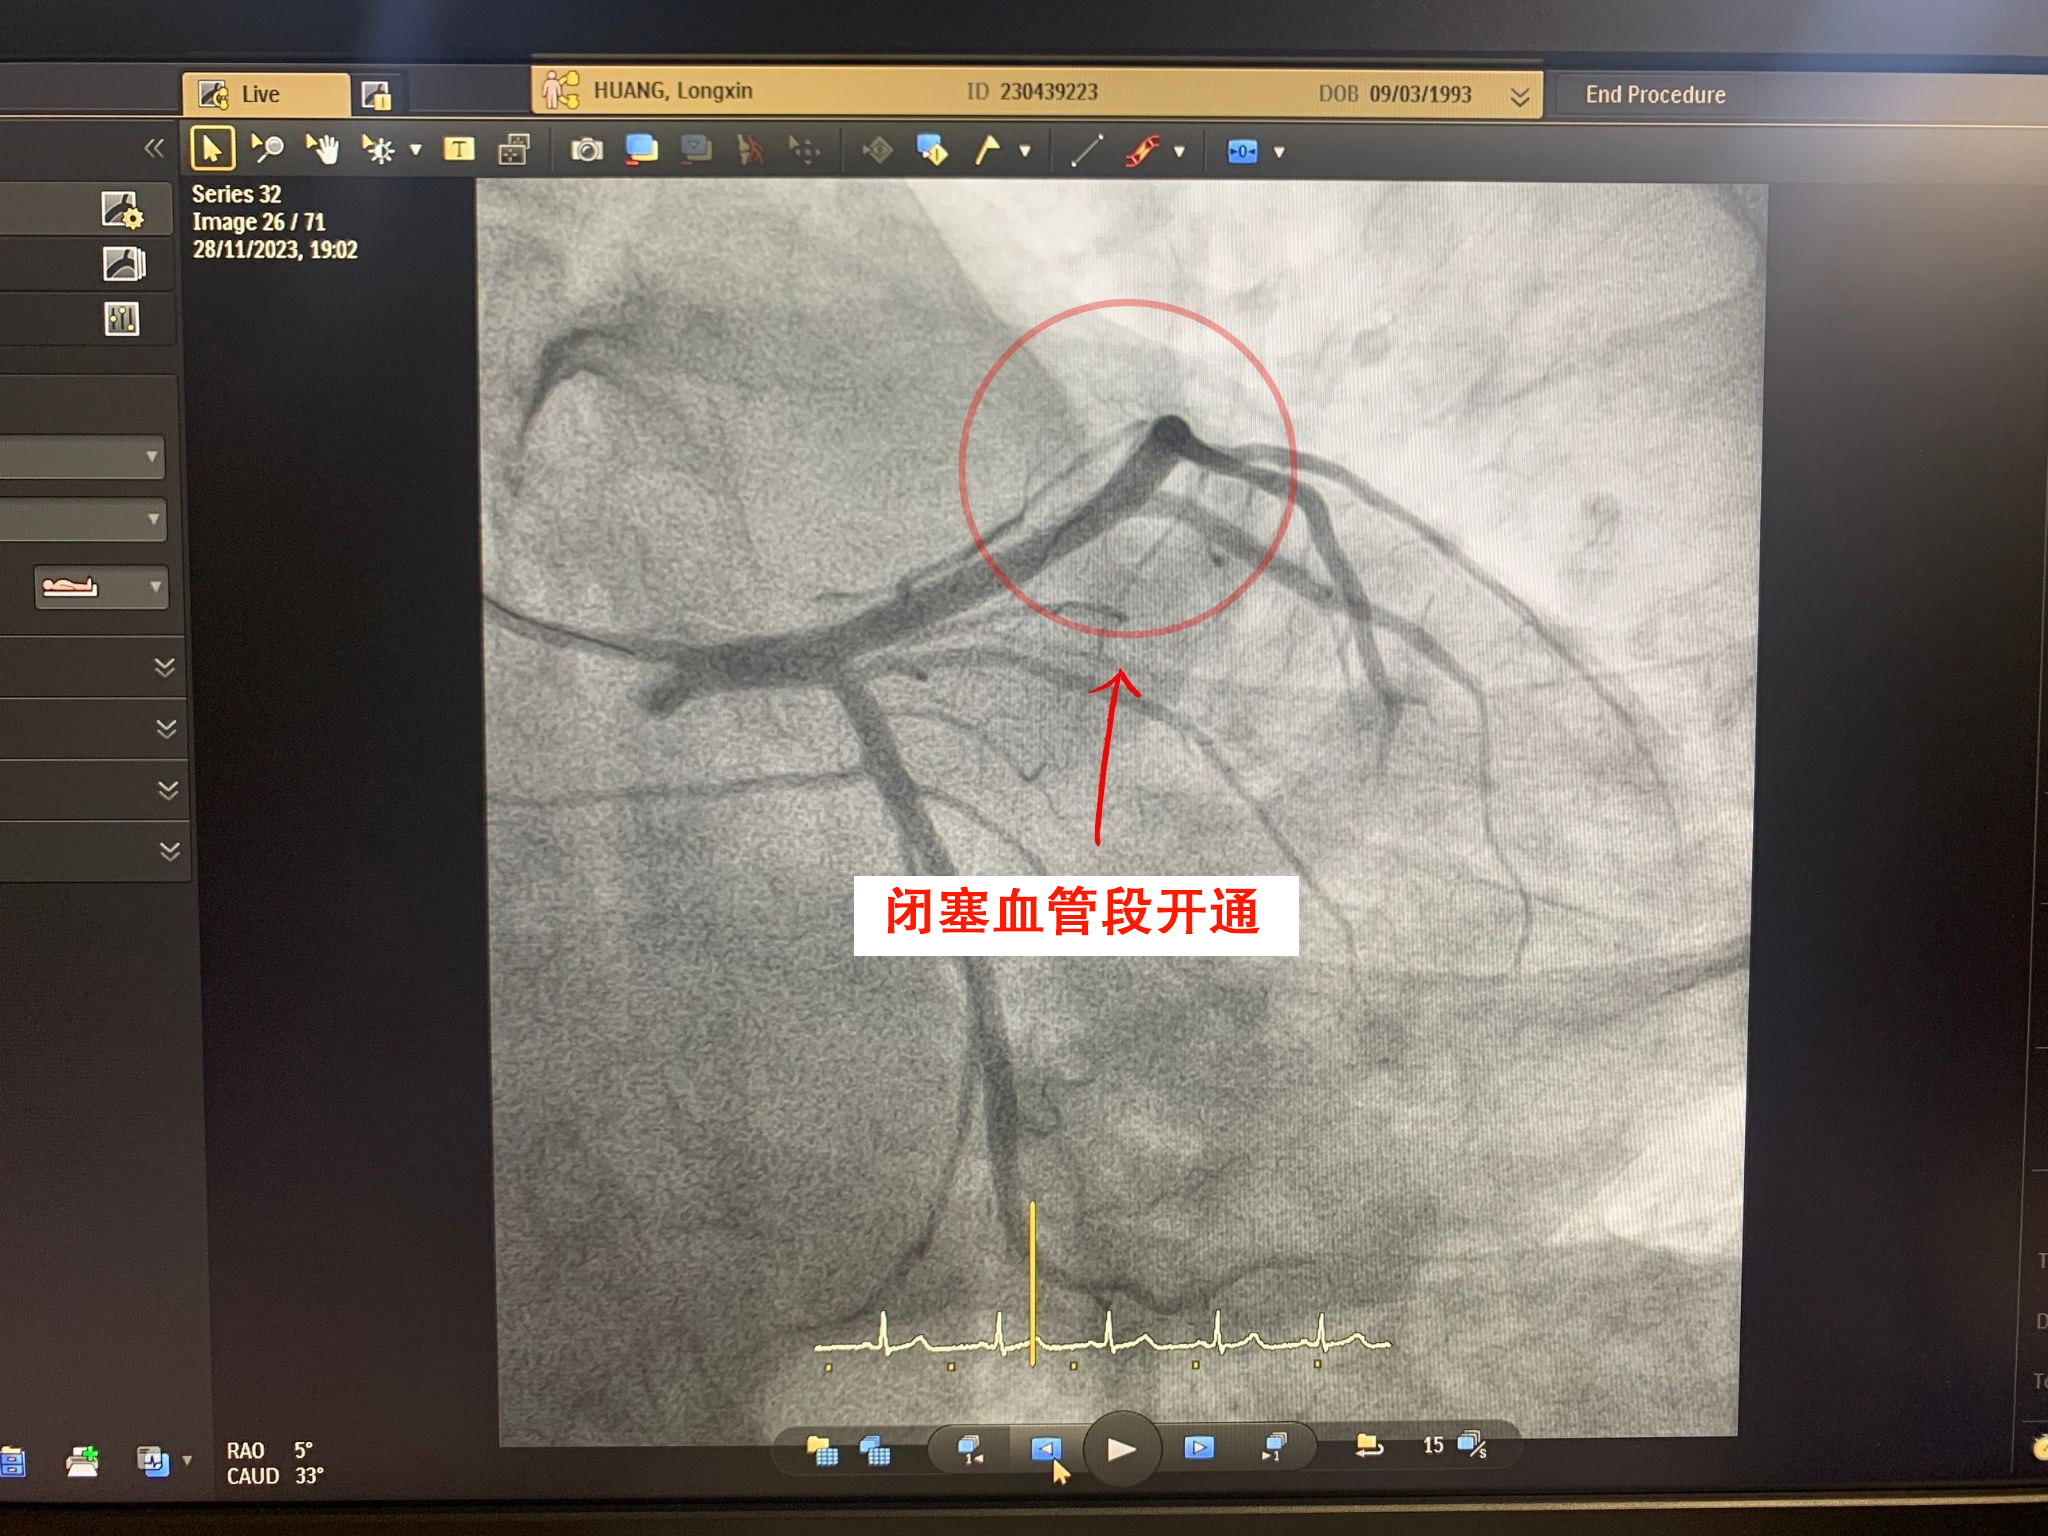

左前降支动脉入口处完全闭塞医疗团队迅速行动,通过血栓抽吸、球囊扩张损伤部位并植入3.5×38(毫米)支架的方式,成功开通闭塞动脉。由于干预及时,最大程度减少了心肌细胞损伤,避免了心律失常、心力衰竭等风险。术后24小时,患者恢复良好,胸痛、头晕、呼吸困难等症状完全消失。

对闭塞血管段进行血运重建并植入3.5×38(毫米)支架H.L先生是一名IT工程师,生活方式‘静态’,肥胖症,体重达100公斤,有超过10年的每天20支以上的吸烟史,且因工作性质经常压力大、熬夜。这是年轻患者常见的不良生活方式,会增加心血管疾病风险,尤其是心肌梗死。